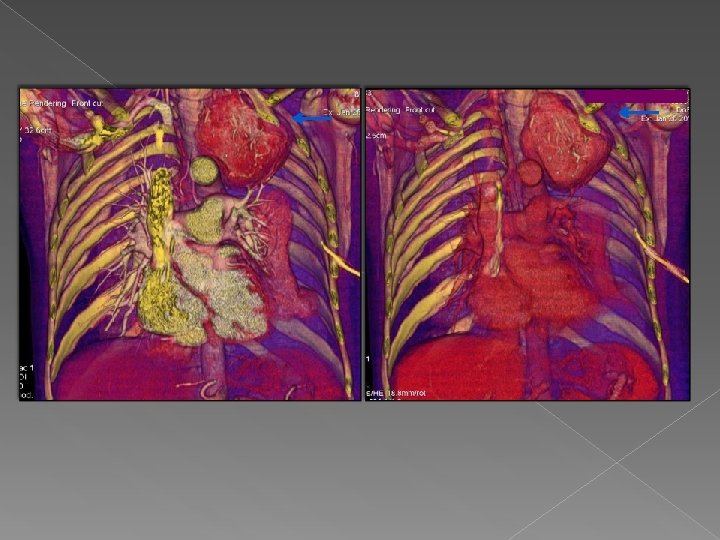

Caso 4 Mujer de 71 años que ingresa por hemoptisis. En reformateo multiplanar y

Caso 4 Mujer de 71 años que ingresa por hemoptisis. En reformateo multiplanar y gracias al MIP se visualiza una arteria bronquial izquierda patológica que se dirige hacia las bronquiectasias de LII. Valor de VR: Visualización del vaso anómalo en todo su trayecto. Identificar con exactitud el origen del mismo de tal manera que los radiologos intervencionistas visualizan la rama que tienen que tratar, la altura del origen y la morfología que adopta facilitando así su trabajo.